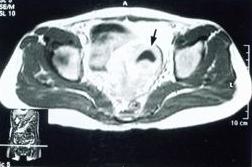

妇科检查时见子宫后屈,活动差,子宫旁可扪及增粗的输卵管,有压痛。如果有炎性包块形成,检查时可在宫旁或子宫后方触及包块,活动不良,有压痛。在女性内生殖器官中,输卵管、卵巢被称为子宫附件。 医学百科网 | YxBaike.Com

盆腔的位置慢性盆腔炎患者早期全身症状多不明显,一般仅为程度不同的、时轻时重的下腹疼痛,或下腹坠胀或牵扯感,月经前、劳累后或性交后加重,并常伴有大便时的腹坠感,白带增多、腰痛、月经失调等,也可因输卵管粘连造成宫外孕或不孕症。

卵巢恶性肿瘤亦可表现为盆腔包块,与周围黏连.不活动,有压痛,与炎性包块易混淆。但其一般健康情况较差,病情发展迅速,疼痛为持续性,与月经周期无关。B超检查有助于诊断。 盆腔淤血综合征 医学百科网 | YxBaike.Com